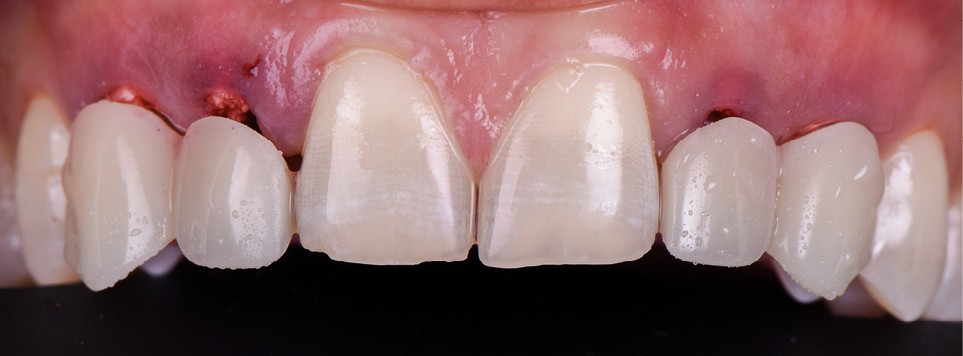

Un homme de 38 ans se présente en consultation d’implantologie pour le remplacement de ses 4 dents lactéales 52 53 62 63. Il ne présente pas d’antécédents médicaux, chirurgicaux, pas d’allergie, est non-fumeur. L’analyse clinique, radiologique et préprothétique fait apparaître (fig. 1) :

- les agénésies de 12 13 22 23 46 ;

- des usures marquées des bords libres des dents lactéales ;

- une égression compensatrice de certaines dents antérieures mandibulaires ;

- un parodonte sain et épais.